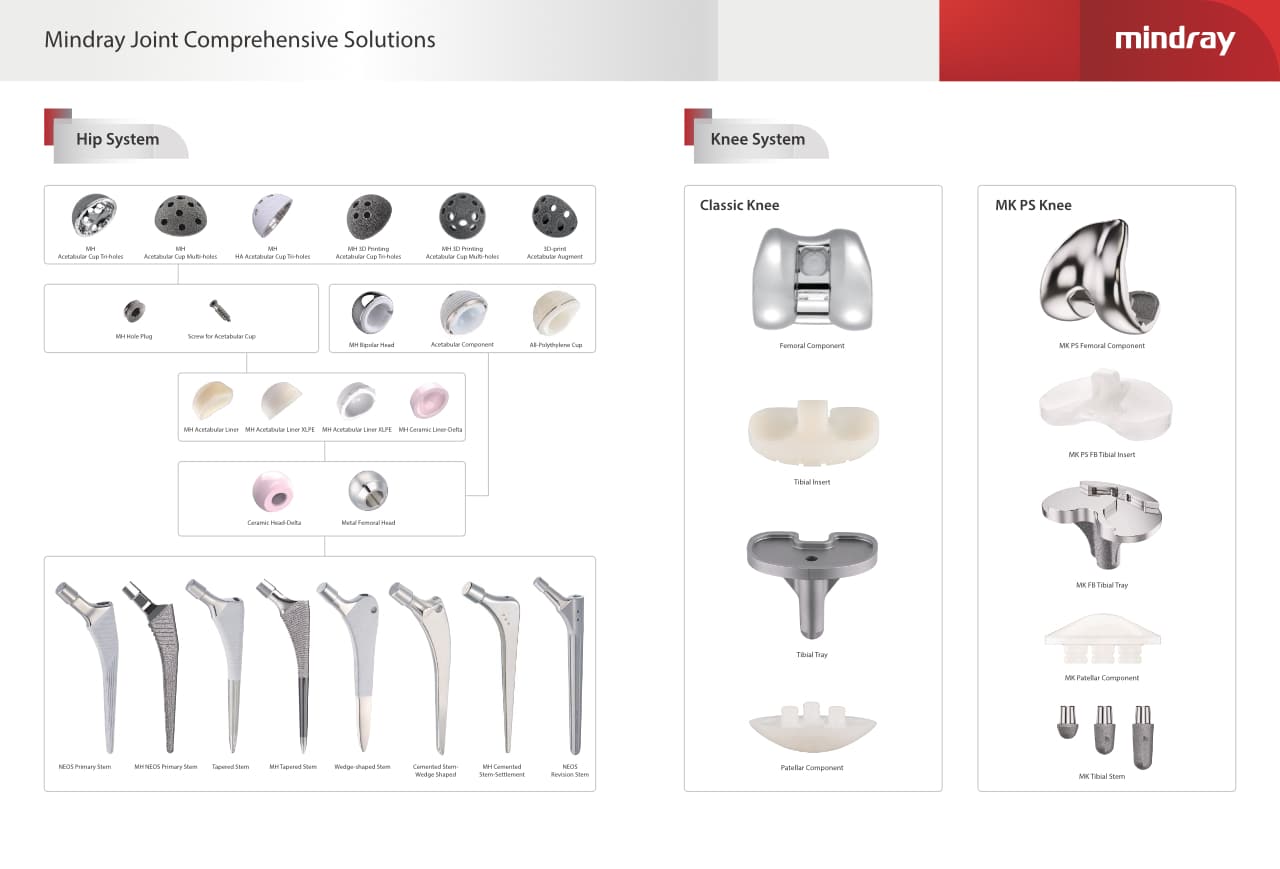

Nos produits dâarthroplastie consistent en deux solutions principales pour les prothÃĻses de la hanche et du genou, y compris lâarthroplastie primaire et la rÃĐvision, selon le type de chirurgie. Les produits dâarthroplastie orthopÃĐdique de Mindray bÃĐnÃĐficient des caractÃĐristiques dâefficacitÃĐ et de stabilitÃĐ classiques.